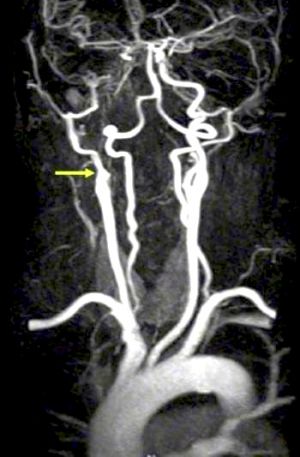

Magnetic Resonance Angiography and Computed Tomographic Angiography

New non-invasive or minimally invasive methods such as magnetic resonance angiography (MRA) (Figure 9) and computed tomographic angiography (CTA) (Figure 10) are increasingly used as second-line investigative tools after duplex ultrasound for carotid stenosis and have gradually replaced DSA .[20]

A review of carotid MRA performance data found that for the diagnosis of 70–99% carotid stenosis, MRA superior pooled sensitivity (95%) and specificity (90%) to conventional DSA.[24] For the detection of complete occlusions, MRA showed similar performance to duplex ultrasound, with a sensitivity of 98% and a specificity of 100%. However, MRA has some limitations, including claustrophobia, pacemakers, obesity, and metallic stents or implantable defibrillators.

Potential advantages of MRA and CTA over conventional angiography include their abilities to allow better carotid plaque characterization and identification and to simultaneously evaluate for cerebrovascular accident.[25] The combined use of MRA, CTA, and doppler ultrasound improves diagnostic accuracy for high-grade symptomatic carotid stenoses and minimizes the need for invasive carotid arteriography. Disadvantages of CTA include the necessity of administering a nephrotoxic iodinated contrast agent and ionizing radiation and the potential for artifacts related to heavily or circumferentially calcified arterial walls.